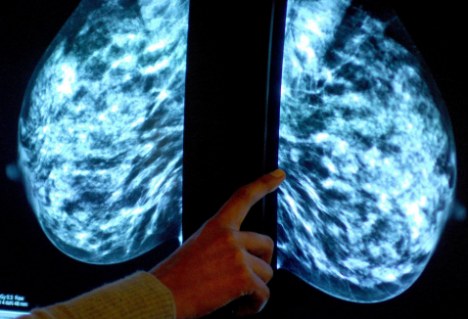

“原為尋找宇宙內(nèi)超新星而設(shè)計的技術(shù),現(xiàn)在正被用于癌癥的診斷。”據(jù)英國《每日郵報》網(wǎng)站3月10日報道,天文學(xué)家現(xiàn)與劍橋大學(xué)的腫瘤學(xué)家組成工作小組,將曾用來區(qū)分單個恒星和遙遠(yuǎn)星系的電腦軟件用于檢測乳腺腫瘤的類別。

發(fā)表在《英國癌癥雜志》的一篇研究報告顯示,研究人員曾使用天文軟件來分析2000名乳腺癌患者的腫瘤情況。報告顯示,該軟件可作出與人類病理學(xué)家一樣準(zhǔn)確的判斷,并在某些情況下,它得出的分析更加客觀。